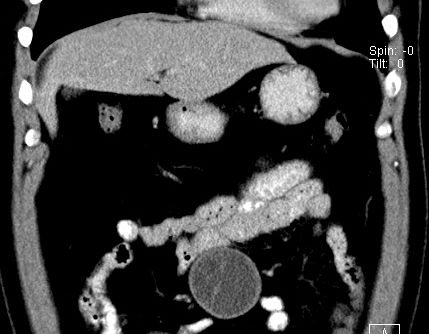

(腹腔)神经鞘瘤

男,48岁,间断性下腹不适1年。

手术探查

:距回盲部28厘米处肠系膜根部可见5*7cm左右包块,质中等硬度,活动度尚可,肝、胆、胰、脾肾未见明显异常。

病理

:(腹腔)

神经鞘瘤

,伴出血、坏死及囊性变,伴淋巴结反应性增生。

免疫组化结果

:sma(-), desmin(-), cd117(-), s-100(+++), nf(-),vimentin(+++).